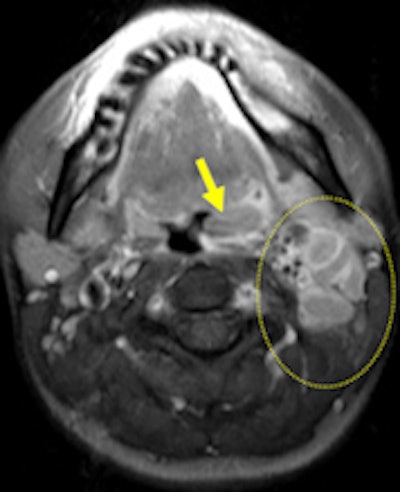

The same patient as seen on postcontrast fat-saturated T1 weighted (left), respectively. Left-sided peripherally enhanced, mostly necrotic, lymphadenopathies (dashed circle) are present on level 2 on axial short tau inversion-recovery and axial postcontrast fat-saturated T1-weighted images. Accompanying minimal signal intensity change and increased thickness of neighboring soft-tissue planes are seen as well. Remarkable restriction of diffusion is illustrated within lyphadenopathies and left palatine tonsil (ADC = 0.82 mm/sn2) (right).The clinical manifestation of tularemia may vary from asymptomatic illness to fulminant toxemia with septic shock, and presentation is dependent on the organism and the route of transmission. Tularemia is traditionally classified into the following clinical types, depending on the route of transmission: ulceroglandular (80%), glandular (15%), oropharyngeal (less than 5%), oculoglandular (1%), typhoidal (less than 1%), and pneumonic (less than 1%). The main symptoms and signs of both the ulceroglandular and glandular form are seen in the head and neck region.